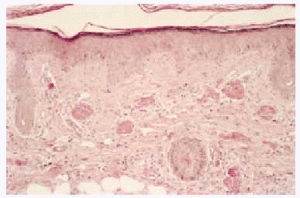

La CGM mixta (tipo II y III) se comporta como una enfermedad mediada por complejos inmunes (CI), capaces de activar el sistema del complemento, tanto por la vía clásica como por la vía alternativa, lo que explica la alta frecuencia de hipocomplementemia en estos pacientes, como ya hemos comentado. Los pacientes podrán presentar la sintomatología típica de una vasculitis sistémica mediada por CI (tabla 1), además de los propios de la enfermedad de base. Como comentamos con anterioridad, son secundarias habitualmente a enfermedades linfo o mieloproliferativas, enfermedades autoinmunes y procesos infecciosos, pero también pueden ser primarias. Con mucha frecuencia las lesiones cutáneas o los fenómenos vasomotores son las manifestaciones iniciales de la CGM. La púrpura es, sin lugar a dudas, la manifestación más frecuente y característica. Se trata de brotes recurrentes de lesiones purpúricas palpables, que comienzan en miembros inferiores, pero que pueden afectar tronco, extremidades superiores y más raramente la cara (figs. 1, 2 y 3). Los brotes pueden precederse de sensación de picor, pero no de auténtico dolor. Duran de 3 a 10 días y dejan huellas de hiperpigmentación. En uno de cada tres pacientes aparecen úlceras en piernas, casi siempre asociadas a púrpura, que frecuentemente se localizan en los maléolos10.

Fig. 3.--Paciente varón con crioglobulinemia tipo II, infección por el virus de la hepatitis C y linfoma de células B no filiado con lesiones purpúricas en tronco y zona axilar.